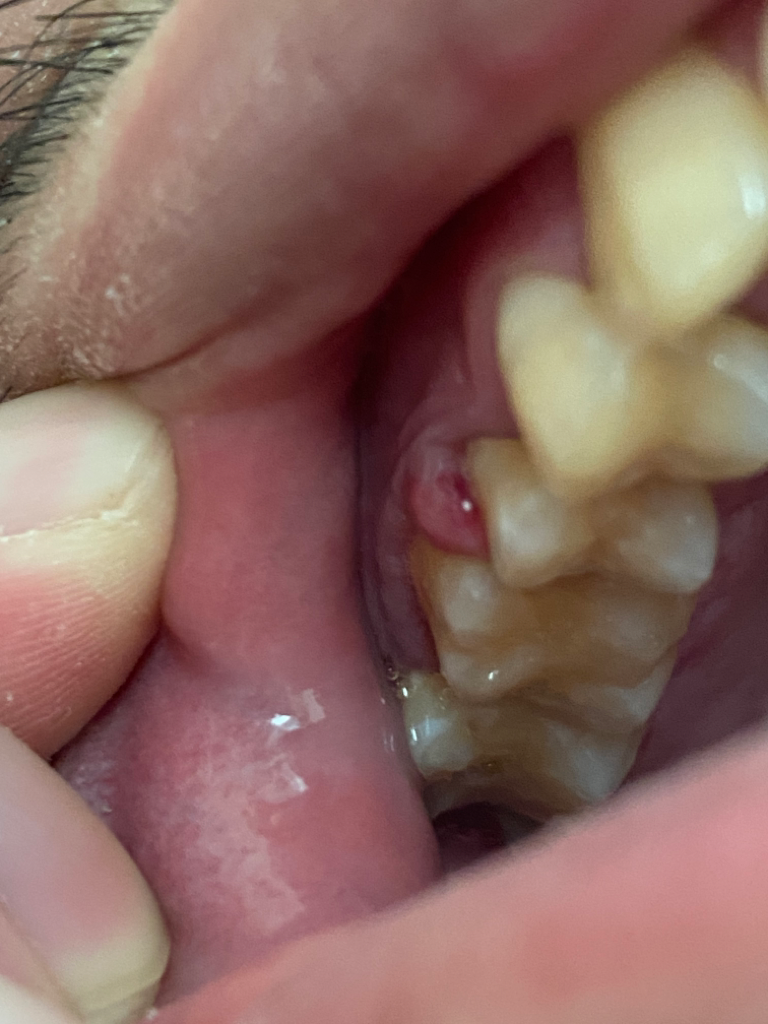

잇몸이 부은 잇몸농양입니다. 당장 급한 것은 아닙니다. 통증 심하면 약국에 파는 일반소염진통제 드시고, 치과에서 가서 부은 부위 터트리거나 절개해 내면 됩니다.

해당 치아에 대해 염증 및 상태가 심해보입니다. 아마 만성적인 염증이 치조골을 뚫고 나왔는 것으로 보여지며 지금 상태에서는 치아에 대한 평가를 받아보셔야 합니다. 통증이 나타나지 않는다면 응급실 방문은 하지 않아도 되나 가급적 치과를 빨리 방문해보시길 바랍니다.

잇몸에 염증이 생기신거 같습니다. 단순한 잇몸염증이라면 크게 문제가 되진않지만, 치아 뿌리에서 염증이 발생한거라면 신경치료를 받으셔야됩니다. 응급실 가실정도는 아니니 평일에 가셔서 검진을 받아보세요.

피가 나고 부어오른 것을 보면 염증이 있는 것으로 판단되며 많이 불편하시면 응급실을 가시는 것이 좋겠습니다.

치석으로 인해 주위조직에 출혈, 통증, 염증이 나타나는 치주염이 원인일수 있고 스켈링과 잇몸치료로 개선이 될 수 있습니다.

치석이 치은연하로 쌓이고 염증이 생기면 치주인대, 치조골이 소실 됩니다.

염증이 심해지면 치아가 흔들리고 발치를 해야 합니다.